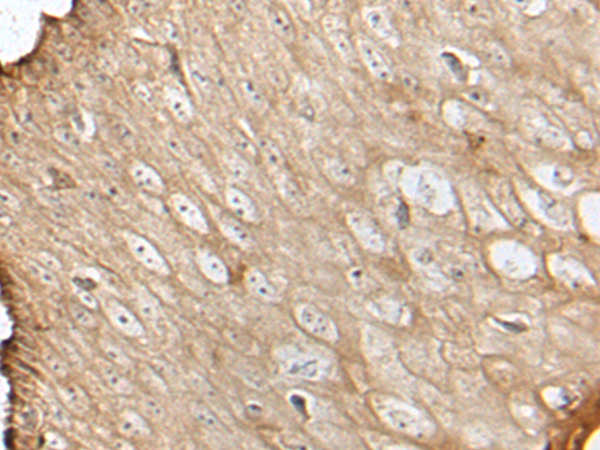

- The image is immunohistochemistry of paraffin-embedded Human esophagus cancer tissue using P12702(KNL1 Antibody) at dilution 1/20. (Original magnification: ×200)